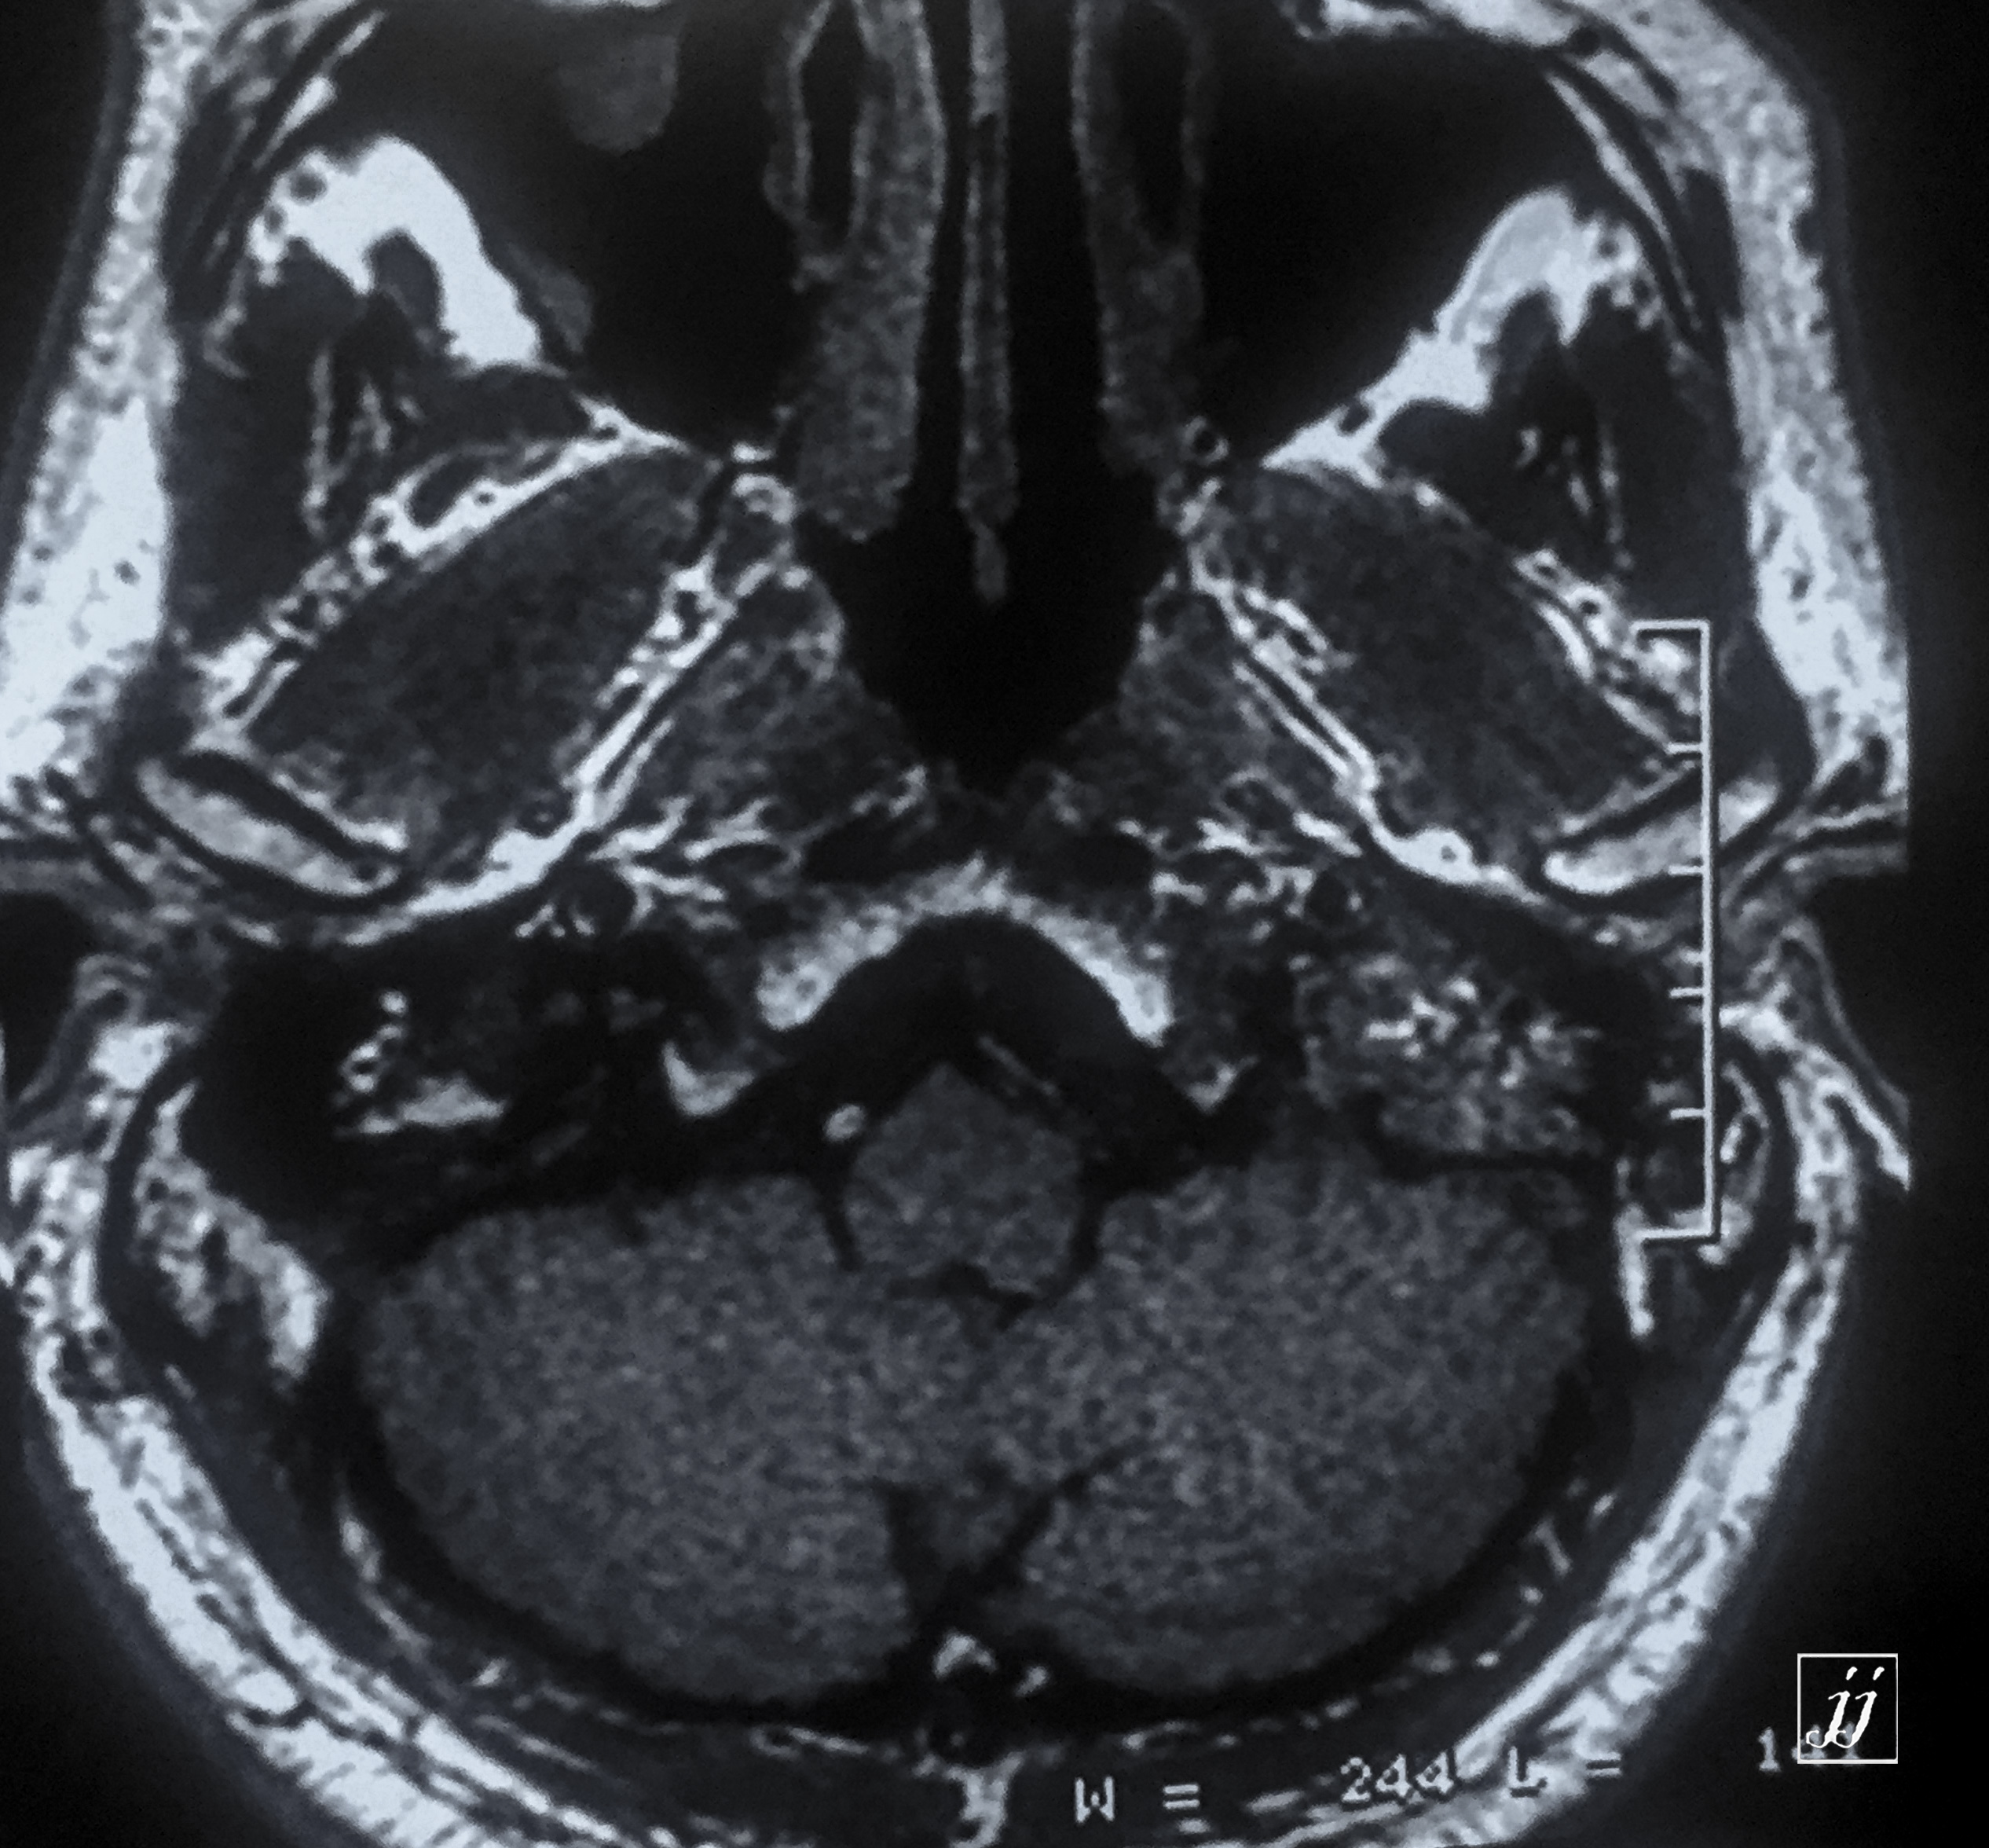

Brain- left side COM (1)